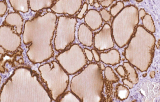

A imunohistoquímica (IHQ) com anticorpos primários CE/IVD é essencial para o diagnóstico e classificação precisos de malignidades ginecológicas e mamárias. Estes anticorpos permitem a deteção precisa de marcadores tumorais e proteínas celulares, apoiando o diagnóstico diferencial e guiando estratégias terapêuticas personalizadas.

Estudos recentes destacam o valor diagnóstico das proteínas do complexo SWI/SNF, particularmente ARID1B, na identificação de malignidades ginecológicas desdiferenciadas e indiferenciadas – tumores agressivos com mau prognóstico. A IHQ de ARID1B oferece elevada especificidade e está cada vez mais integrada em painéis diagnósticos para melhorar a precisão. Painéis com marcadores adicionais também apoiam a diferenciação de sarcomas uterinos, aumentando a exatidão diagnóstica. Evidência emergente sugere que ARID1B pode representar um alvo terapêutico potencial no carcinoma ovárico de células claras, embora as aplicações clínicas permaneçam em fase investigacional.